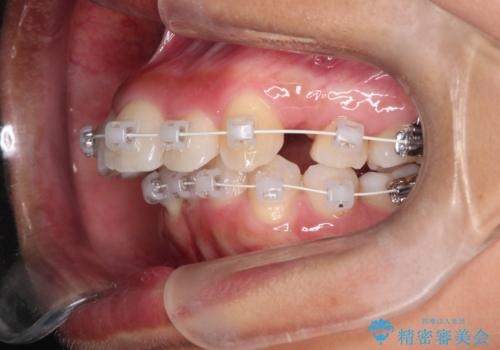

- 矯正装置

- 審美装置

- 前歯の凸凹を主訴に来院されました。

抜歯を行い、ワイヤー矯正にて治療を行いました。

CTにて骨を確認し、側切歯の歯根をこれ以上頬側に出せないことを確認しています。